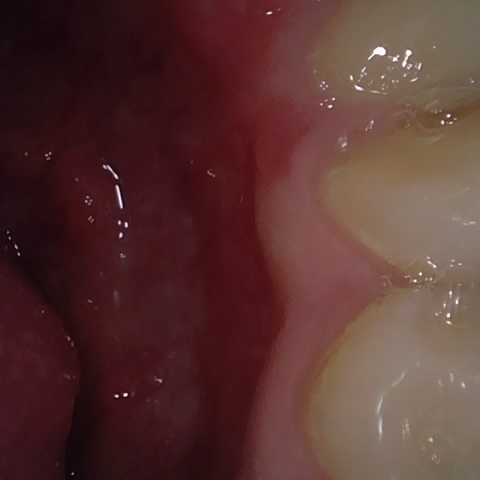

Annotated as "Good"